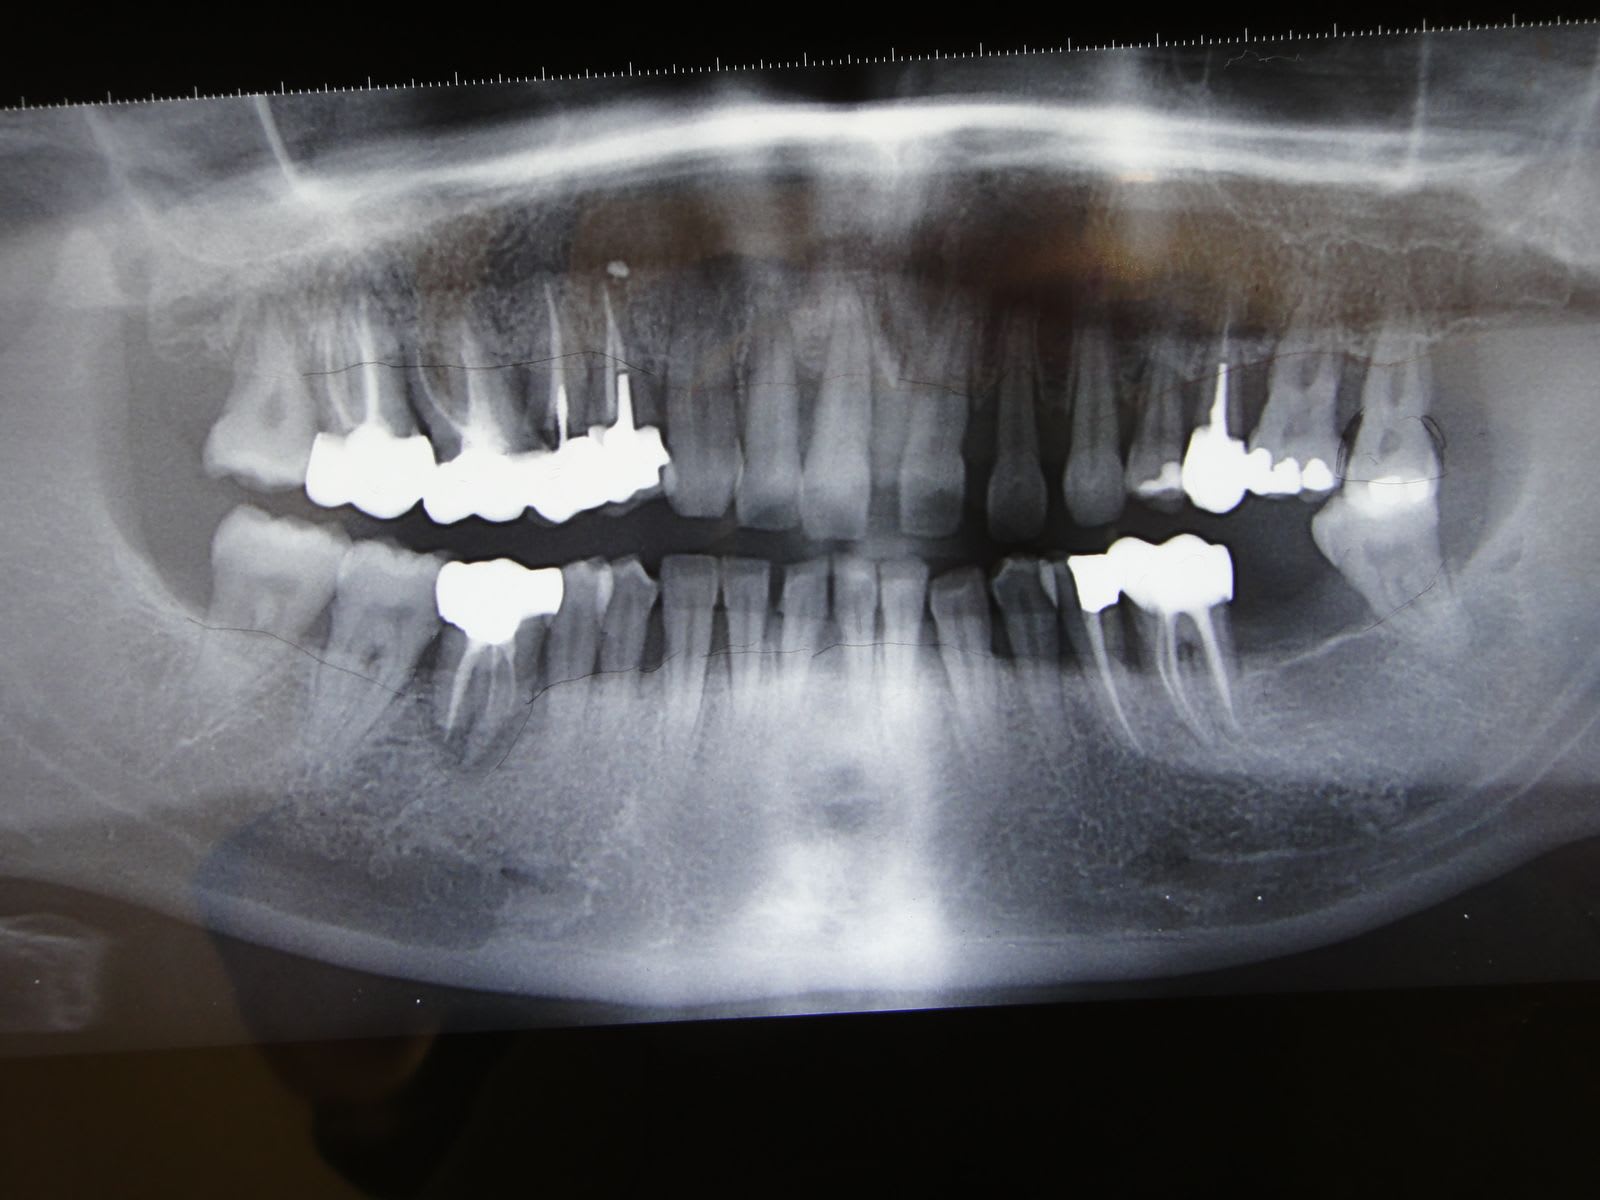

En 2011 elle revient pour des dents antérieures sup qui commencent à migrer et une esthétique qui lui déplait. voici l'OPT de départ.

Le temps qu'elle se décide à faire quelque chose on se retrouve en 2013 avec cette photo du secteur antérieur.